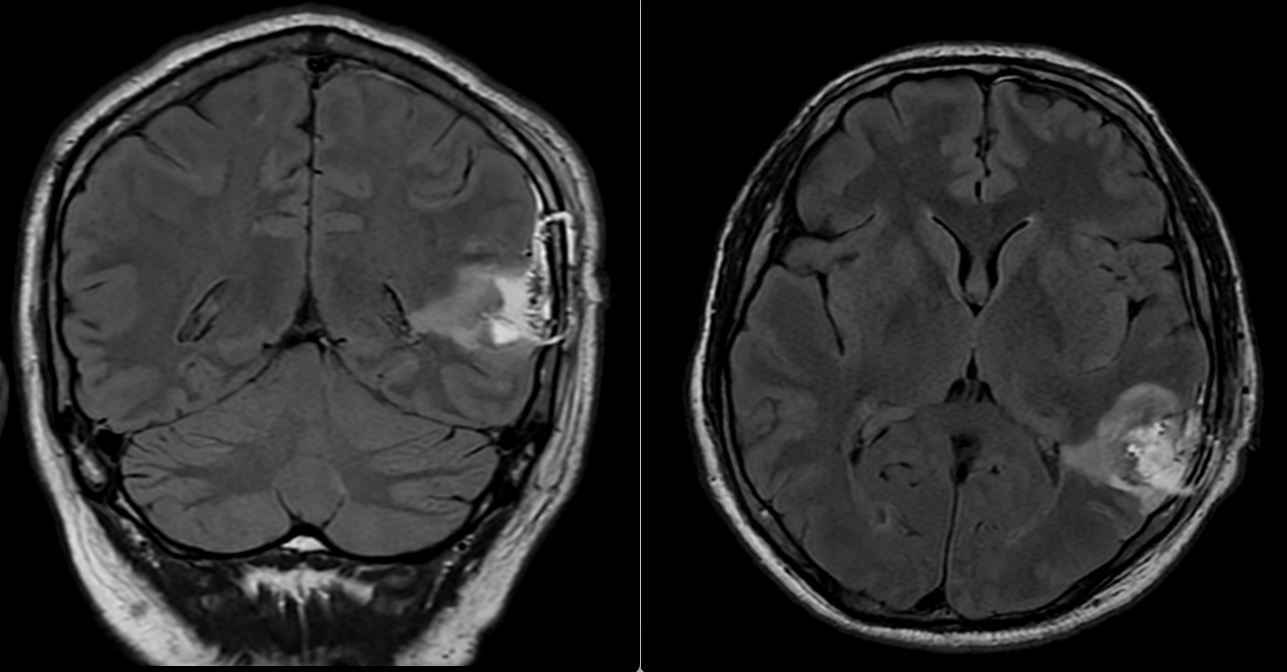

Postoperator, evoluția imediată a fost foarte bună. Pacientul a avut o stare generală și neurologică excelentă, fără niciun deficit nou, iar CT-ul cerebral de control nu a evidențiat complicații locale, precum hematom sau alte colecții postoperatorii. RMN-ul cerebral efectuat ulterior a arătat că a rămas un rest tumoral în substanța albă profundă a emisferului stâng. Acest aspect este important și trebuie explicat clar pacienților: în chirurgia glioamelor infiltrative din ariile elocvente, uneori nu cea mai agresivă rezecție este cea mai bună opțiune, ci cea care păstrează echilibrul între controlul oncologic și păstrarea funcției neurologice.

La 1 an după operație, controlul imagistic a arătat o reducere semnificativă a restului tumoral de la nivelul pereților cavității de rezecție, acesta devenind aproape imperceptibil pe unele secvențe. Clinic, pacientul avea o viață normală, fără deficite neurologice și fără crize epileptice.